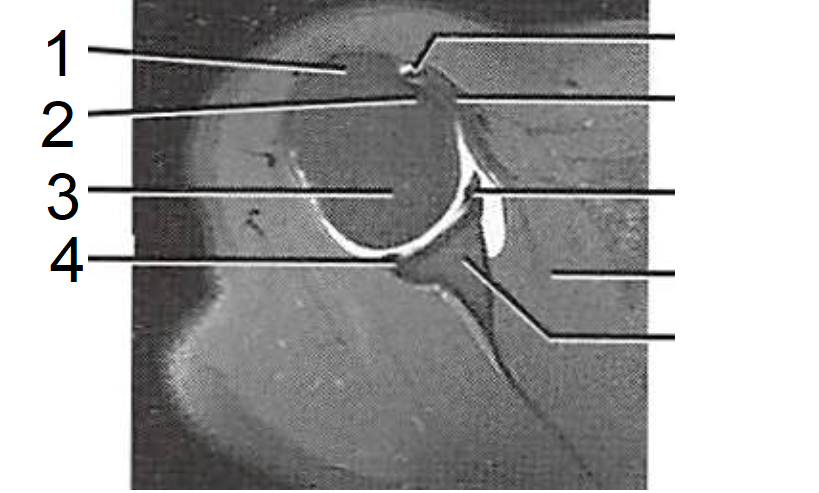

6

1 - M. supraespinhal

2 - Lábio articular, superior

3 - Cavidade glenoidal

4 - Tubérculo maior